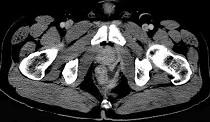

问题 男,28岁,高热,肛门坠胀,频有便意,直肠指诊时触及直肠粘膜下饱满,柔软,压痛的肿块,CT检查如图,诊断为 ( )

选项 A.直肠癌 B.直肠炎性息肉 C.直肠粘膜下脓肿 D.直肠绒毛状腺瘤 E.直肠粘膜下瘘

答案 C